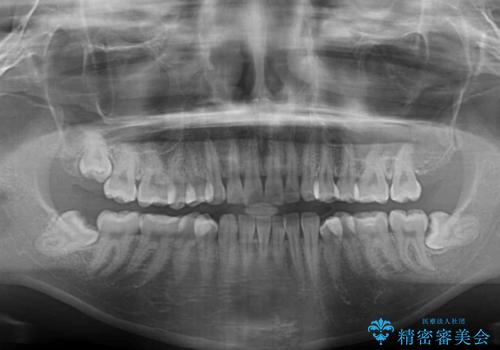

- 上下前歯が非接触となり、前方に突出していることを気にして来院された患者様です。

咬合力が強く、全体的に歯がすり減っているため、インビザライン単独での上顎歯列移動は困難と判断し、補助装置により上顎歯列を後方移動させ、その後インビザラインにて仕上げていくこととしました。